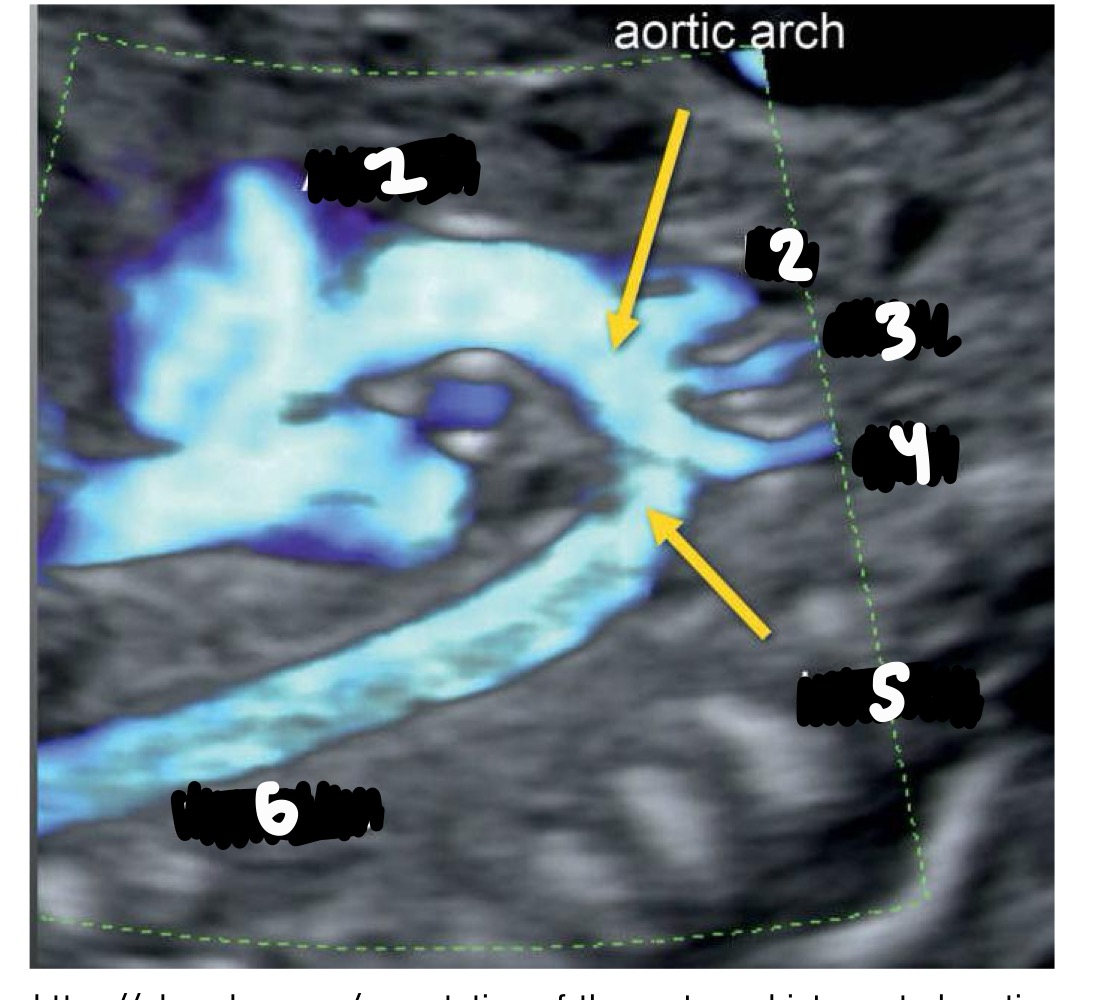

What is the shape of the aortic arch

Candy cane (tight curve)

What branches arise from the aortic arch IN ORDER

Brachiocephalic, left common carotid, left subclavian

Ascending aorta

Innominate/brachiocephalic artery

Left common carotid

Left subclavian artery

Isthmus

Descending AO